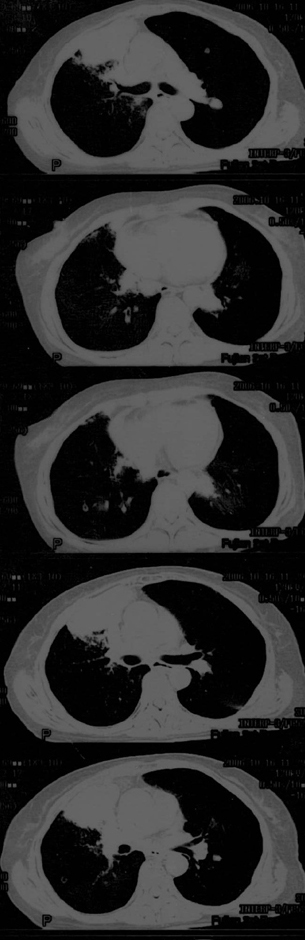

母亲67岁,咳嗽,无血痰。发病已两月余,抗生素无效

传上图片看不清,可是给我的感觉是恶性的,虽然还需跟肺结核相鉴别.

片子不清,右肺下叶像个结核球,右肺上叶需要做个支气管镜检查,除外中心型肺癌。个人意见,其他老师们再看看。